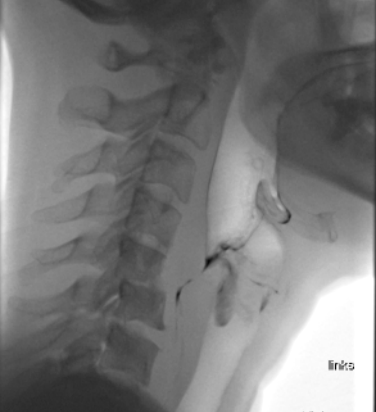

Die Auswirkungen einer Schluckstörung, z.B. nach einem Schlaganfall, bei einer Demenzerkrankung oder einem Tumor im Mund-Rachen-Bereich, auf die Lebensqualität und die Gesundheit sind weitreichend. Lange wurden Schluckstörungen mit Anpassungen wie Eindicken von Flüssigkeiten oder Pürieren von fester Nahrung behandelt. Viele jüngere Studien zeigen aber, dass Eindicken keine Komplikationen verhindert. Denn der Körper reagiert mit einer Reihe von Schutzmechanismen, wenn fremdes Material in die Lunge gelangt. Für die Lunge sind aber die Bakterien im Mund am gefährlichsten. Deshalb ist es wichtig, dass die Zähne regelmässig mit Zahnbürste und Zahnpasta geputzt werden, auch wenn man aufgrund einer Schluckstörung gar nichts essen oder trinken kann. Eingedickte Flüssigkeiten führen zusätzlich zu einer feinen Schicht auf der Mundschleimhaut, wo sich die gefährlichen Bakterien besser absetzen und vermehren können. Dadurch steigt das Risiko für eine Lungenentzündung.

Es kann bei einer Schluckstörung vorkommen, dass die Muskelkraft zum Kauen nachlässt. Dies kann dazu führen, dass ein Stück des Steaks die Luftwege blockiert. Diese Gefahr muss logopädisch abgeklärt werden. Das bedeutet aber nicht zwingend, dass das Steak püriert werden muss. Eine Alternative kann sein, es in weiche Würfel kleiner als 1,5 cm zu schneiden (Mindestgrösse der Luftröhre). Mit dieser Kostform wird die Kaumuskulatur ohne das Risiko einer Blockierung der Luftwege trainiert. Im Vergleich zur pürierten Kost bleiben sogar weniger Reste im Hals stecken, die unbemerkt und kontaminiert mit Bakterien in die Lunge gelangen können.